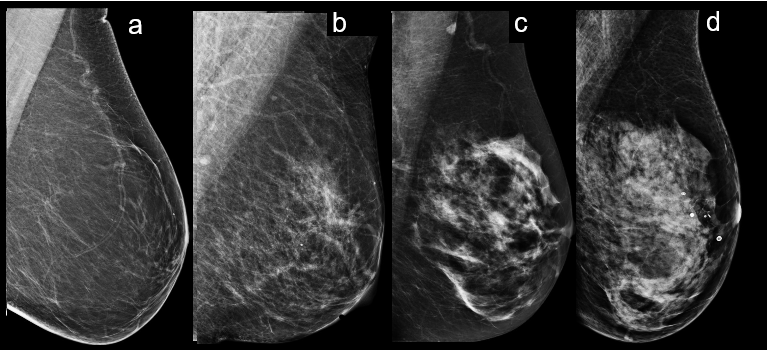

Historically, breast density was measured by estimating the area of parenchymal or fibroglandular tissue (lighter shade of grey on mammography) to the total area of the breast including fatty tissue (darker grey) on a 2 dimensional mammogram. A radiologist can describe their visual assessment of breast density quantitatively as a percentage (0-100%) or as a quartile ranking using a standard reporting system called the Breast Imaging Reporting and Data System (BI-RADS) encoded as “a” to “d” (3). A verbal, or semi-quantitative description with terms such as fatty, mixed and dense breasts is sometimes included in mammography reports.

The introduction of digital mammography permits estimation of fibroglandular volume (FGV) compared to total breast volume, usually calculated in cubic centimetres (cc). This can be expressed as a continuous measure of absolute FGV and percentage volumetric breast density (VBD) which ranges from 0% to around 30% in very dense breasts, or can be related to the BI-RADS 5th edition descriptors (2). We are also interested in observational rating of density by a radiologist as percentage on a visual analogue scale (VAS) which, although subjective, correlates with breast cancer risk and therefore appears to include qualitative information that is not captured by the volumetric analysis (4).

We used a variety of breast density measures to compare the outcomes of cases with controls including categorical measures (FGV quartile, VAS quartile and density grade (DG) “A” to “D”) and continuous measures (FGV, VBD, VAS). We used a proprietary breast density assessment tool (Volpara TM) (6) to analyse the raw mammogram data and an experienced breast Radiologist to score the percentage density on VAS.